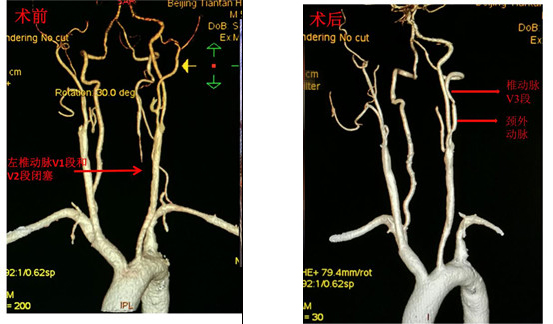

椎动脉V1段狭窄可以进行介入或手术治疗,而V1段闭塞或合并V2段闭塞一般就需要手术治疗。北京天坛医院血管外科常规开展椎动脉外科手术治疗,如椎动脉—颈总动脉转位术(把颈总动脉的血液引入病变的椎动脉,改善椎动脉及大脑的血供),椎动脉V3段—颈外动脉转流术(把颈外动脉的血液引入病变的椎动脉,改善椎动脉及大脑的血供)等。通过这些手术可以解决椎动脉不同部位的闭塞或者狭窄,改善大脑的血供,预防脑梗的发生。

颈外动脉—椎动脉V3段转流术

椎动脉—颈总动脉转流术